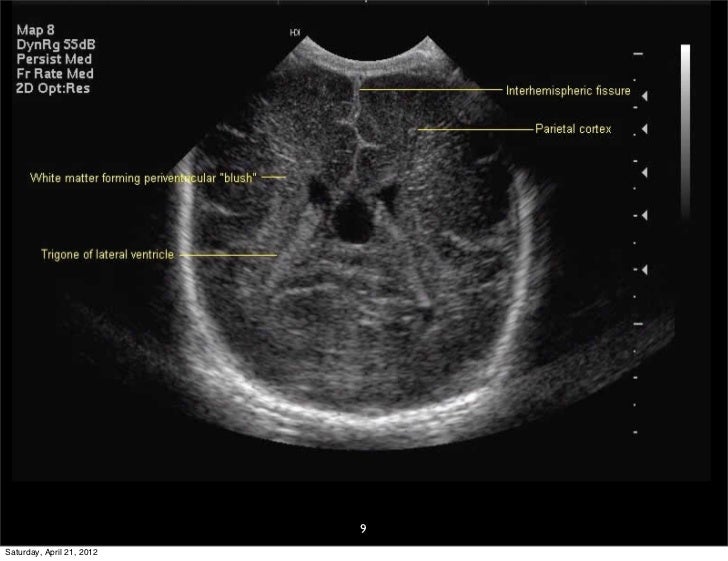

Прозрачная перегородка узи

Прозрачная перегородка узи 109 фотографий